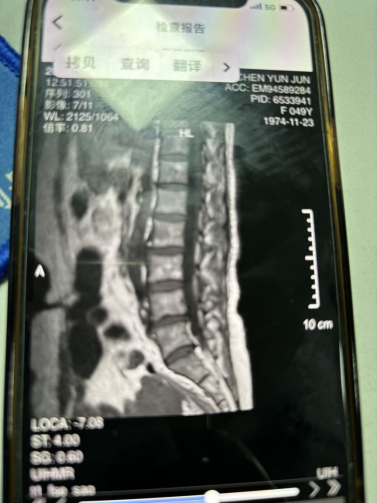

二、病史:患者20余年前无明显诱因下出现腰痛,期间至当地医院治疗断断续续,症状时轻时重。1月前自觉右侧臀部疼痛,伴有右下肢放射痛麻木,甚则放射至脚趾,前往恩泽医院就诊,诊断为“腰椎间盘突出症”行腰椎MRI提示:“腰4-5椎间盘右后脱出,腰5/1椎间盘左后突出;腰4-1椎管狭窄;腰4-5终板炎;腰椎退行性变”。近期患者自觉症状逐渐加重,故来我院针灸科门诊求诊。

四、辅助检查:外院腰椎MRI提示:“腰4-5椎间盘右后脱出,腰5/1椎间盘左后突出;腰4-1椎管狭窄;腰4-5终板炎;腰椎退行性变”。